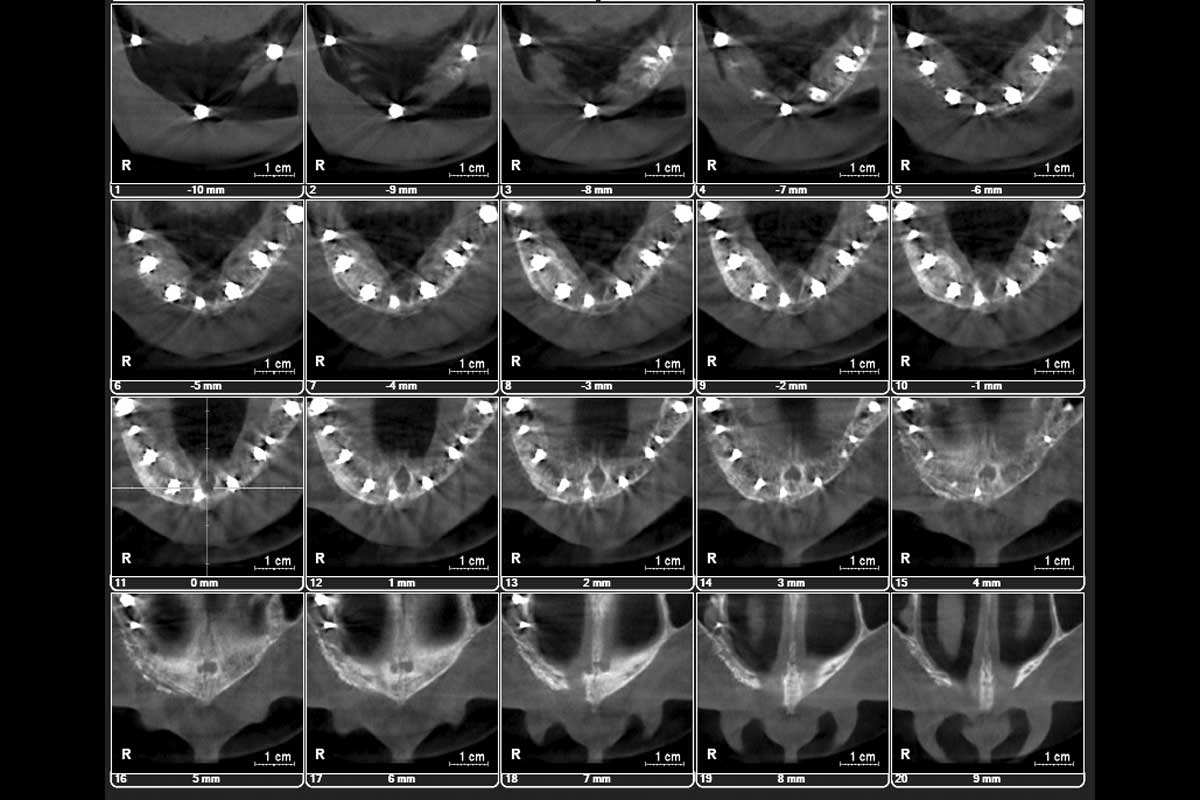

Initial x-ray showing bone loss around implants placed 5 years ago in another dental clinic